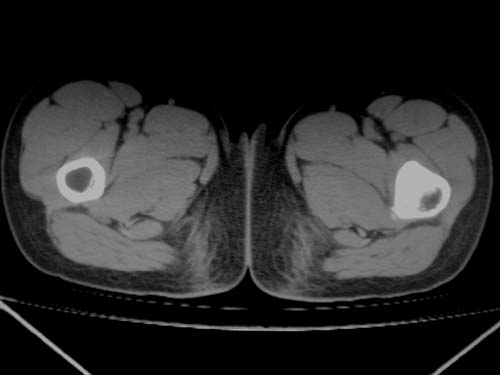

标题: CT19608:女12岁,左髋部疼痛,无发热病史 [打印本页]

标题: CT19608:女12岁,左髋部疼痛,无发热病史

左股骨干增粗,磨玻璃样改变——考虑骨纤维异常增殖症!

左股骨干增粗,磨玻璃样改变——考虑骨纤维异常增殖症!骨化性纤维瘤?